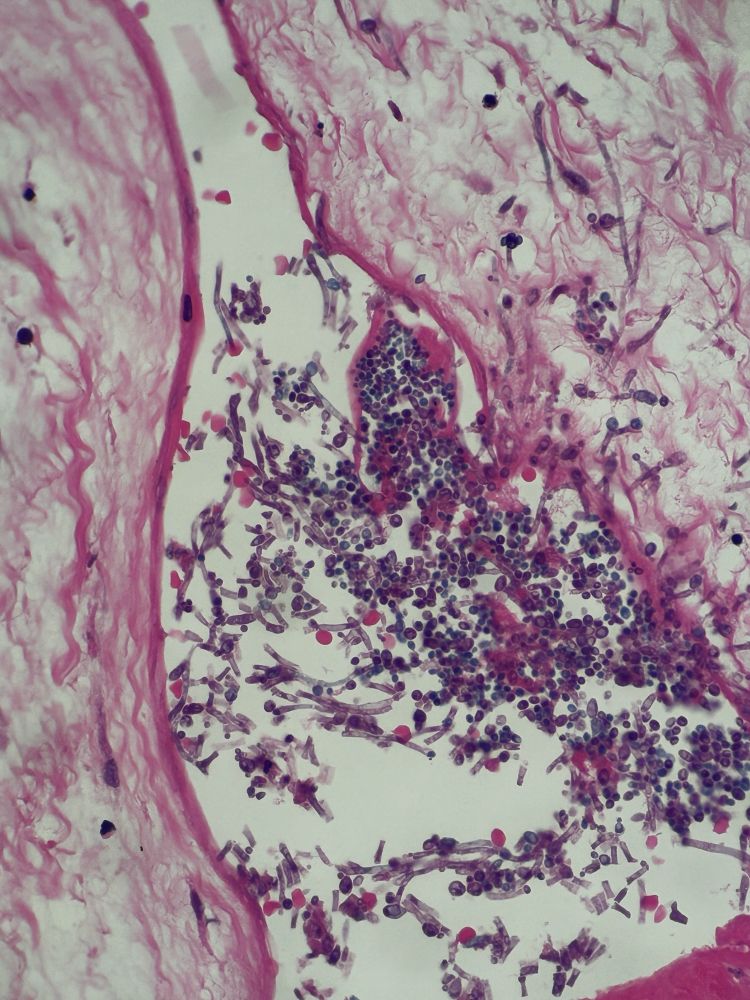

PAS or Grocott not required here 😬

#PathSky

A slightly degenerate example of cryptococcus, which seems a bit nicer than met Ca.

PAS and mucicarmine

22.05.2025 08:47 β€” πŸ‘ 1    πŸ” 0    πŸ’¬ 1    πŸ“Œ 0

Post image

PET-avid 🫁 lesion, hx of SCC elsewhere, biopsied.

22.05.2025 08:47 β€” πŸ‘ 2    πŸ” 0    πŸ’¬ 1    πŸ“Œ 0